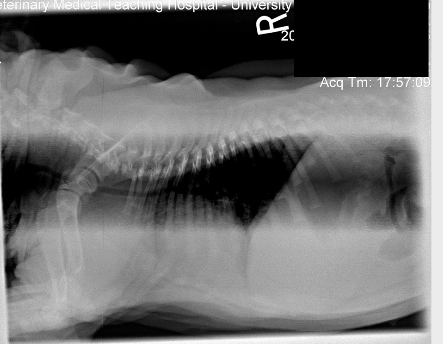

Critiquez l’exposition de cette radiographie.

A) elle est adéquate

B) elle est sous-exposée

C) elle est surexposée

D) l’appareil est défectueux

C)